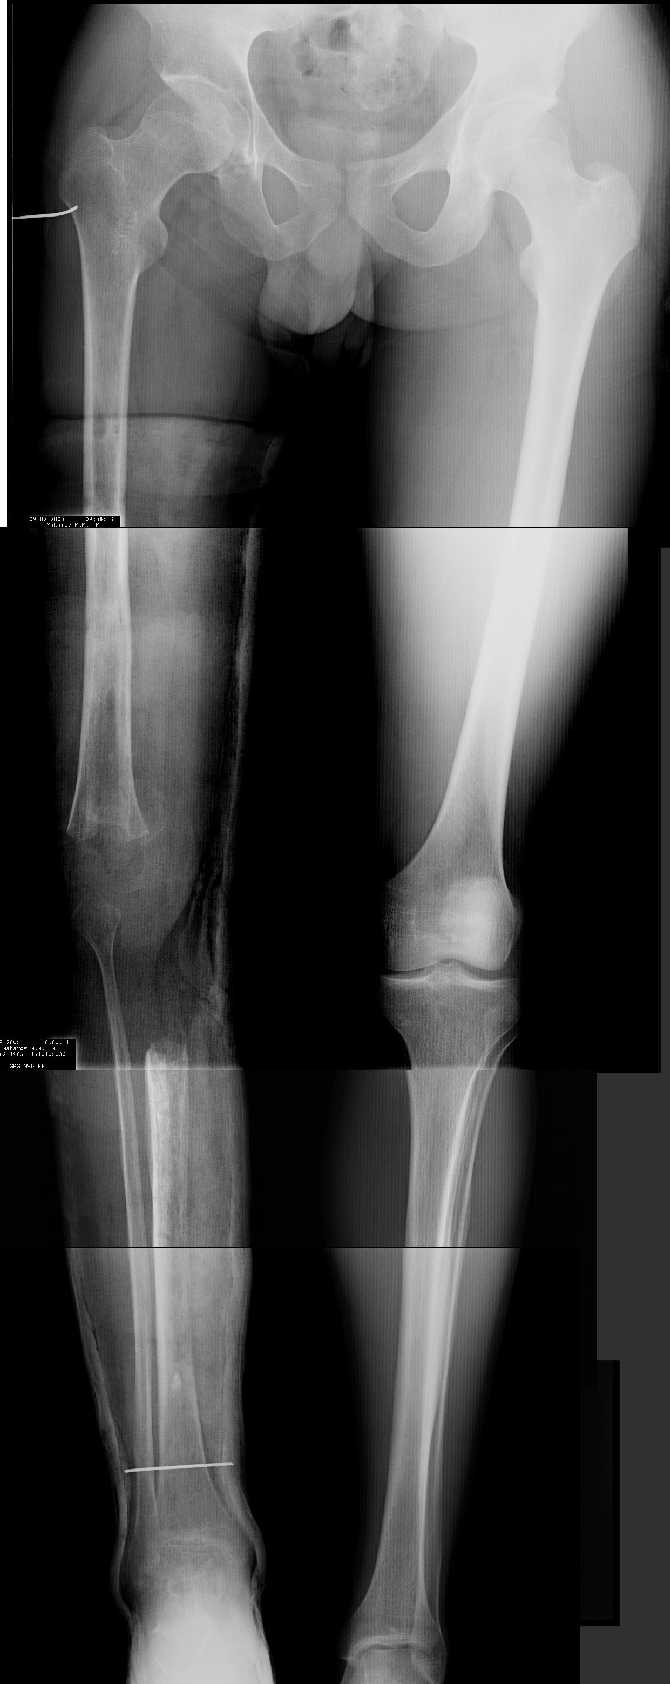

AV> многооскольчатый перелом правой бедреннойљ кости на границе

AV> средней и нижней трети со смещением,

AV> В настоящее время стойкая разгибательная контрактура правого

AV> коленного сустава (сгибание 105-110 гр., разгибание 160-165 гр.),

AV> варусная деформация, болевой синдром.

имеется S-образная деформация бедра на фоне "многооскольчатого

перелома правой бедреннойљ кости на границе средней и нижней трети со смещением"

(хотя "длинные" снимки конечно же не помешали бы...)

На представленных снимках эта деформация как раз и не представлена.

1. Иллюстрации - во вложении.

Два бедра после эндопротезирования.

Авторы операции долго думали почему больная хромает.

Сдклали снимок - одна нога короче почти на 3 см.